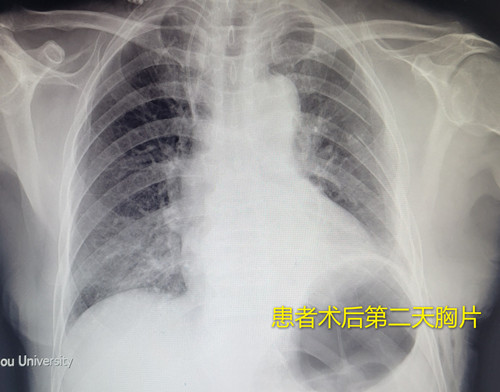

12月27日,胸外科成功完成我院首例“支气管重建—左肺下叶袖式切除术”,患者术后恢复良好,复查结果满意。

手术当天,郭虹和胸外科副主任范黄新、主任医师刁亚利、副主任医师施庆彤等紧密配合,在麻醉科、手术室的通力协作下,切除左下肺中央型肺癌,完成左上肺支气管与左主支气管气道重建。手术历时2个多小时,过程顺利,术中患者生命体征平稳,气道重建满意。